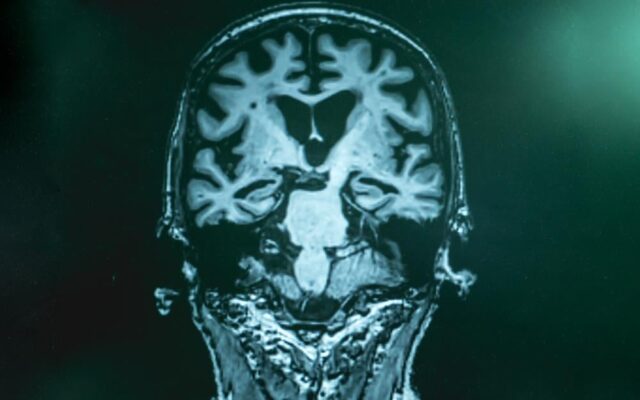

«Τώρα αρχίζουμε να συνειδητοποιούμε πόσο αργή μπορεί να είναι η εξέλιξη της ασθένειας», δήλωσε ο Ronald Postuma, καθηγητής νευρολογίας και νευροχειρουργικής στο Πανεπιστήμιο McGill του Μόντρεαλ. «Προχωράει στον εγκέφαλο, χρόνο με το χρόνο, μέχρι να φτάσει στο όριο κατά το οποίο οι γιατροί μπορούν να κάνουν τη διάγνωση».

Η νόσος βλάπτει τους νευρώνες που παράγουν ντοπαμίνη, χημική ουσία που μεταδίδει σήματα μεταξύ των κυττάρων και παίζει καθοριστικό ρόλο στον έλεγχο της κίνησης και του συντονισμού στον εγκέφαλο. Μέχρι να εμφανιστούν τα κινητικά συμπτώματα, το 50-70% , μιας μικρής αλλά ζωτικής σημασίας δομής για την εκούσια κίνηση που βρίσκεται στο στέλεχος του εγκεφάλου, έχει ήδη «πεθάνει».